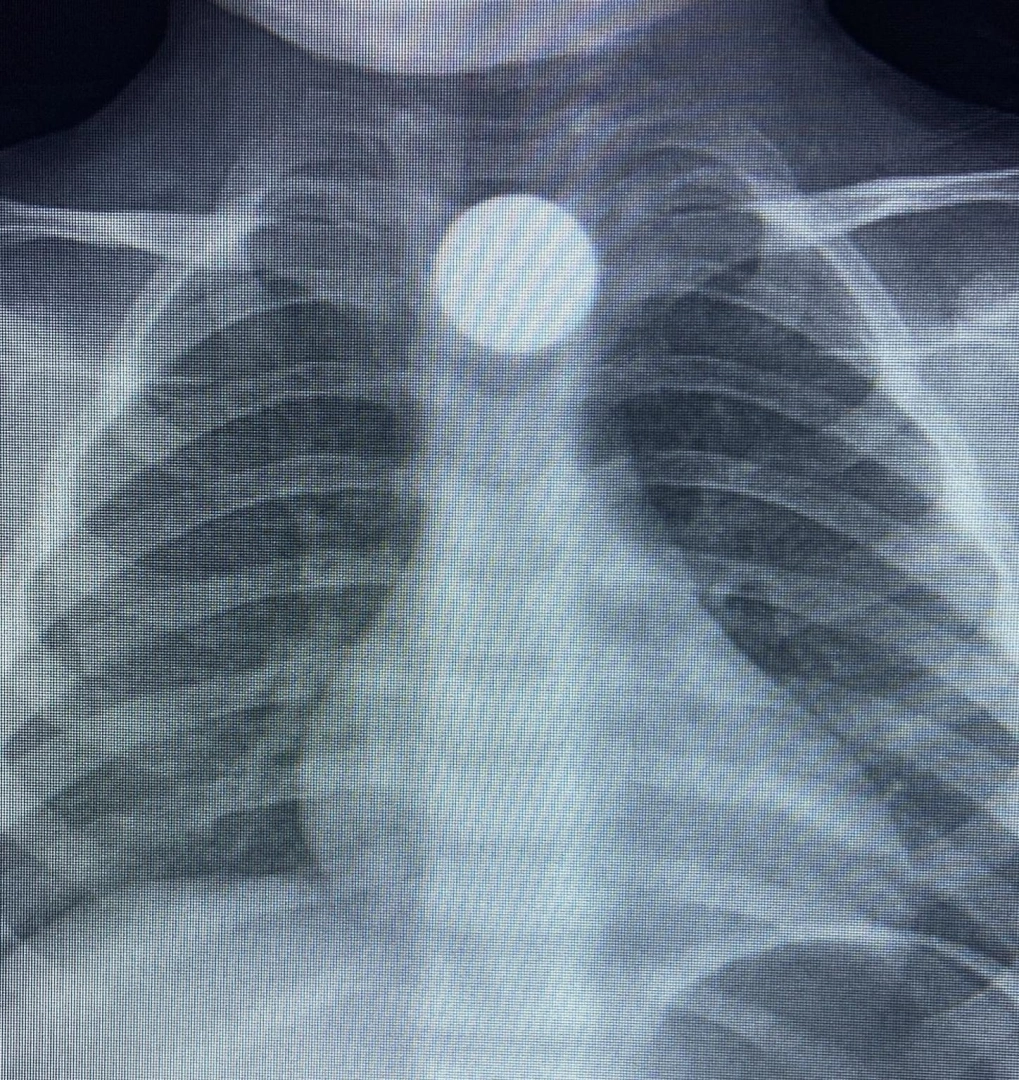

Olay, kırsal Yeniceköy Mahallesi’nde meydana geldi. Bilal K., evde oynarken yerde bulduğu 50 kuruş madeni parayı ağzına alıp yuttu. Durumu fark eden ailesi, Bilal K.’yi özel araçla İnegöl Devlet Hastanesi’ne götürdü. Hastanede yapılan kontrollerde, madeni paranın Bilal K.’nin yemek borusunda takılı kaldığı belirlendi. Burada ilk müdahalesi yapılan Bilal K., daha sonra ambulansla Bursa Yüksek İhtisas Eğitim ve Araştırma Hastanesi’ne sevk edildi.